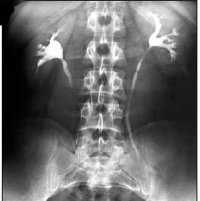

- УЗИ почек. Проводится в положении стоя и лежа, отражает локализацию почки, изменения ее расположения в зависимости от положения тела. С помощью сонографии удается выявить воспаление в почечной ткани, конкременты, гидронефротическую дилатацию чашечно-лоханочного комплекса. Проведение УЗДГ сосудов почек необходимо для визуализации сосудистого русла почки, определения показателей кровотока и степени нарушения почечной гемодинамики.

- Рентгенодиагностика.Экскреторная урография позволяет оценить степень патологического опущения почки по отношению к поясничным позвонкам, ротацию почки. Обзорная урография при нефроптозе, как правило, неинформативна. Проведение почечной ангиографии и венографии требуется для оценки состояния почечной артерии и венозного оттока. Высокоточной и информативной альтернативой рентгеноконтрастным методам служат КТ, МСКТ, МРТ почек.

Распознавание нефроптоза основывается на жалобах пациента, данных осмотра, пальпации почки, результатах лабораторной и инструментальной диагностики. Обследование выполняется в положении больного не только лежа, но и стоя. Проведение полипозиционной пальпации живота позволяет выявить подвижность и смещаемость почки. Измерение и мониторинг АД показывает увеличение значений кровяного давления на 15-30 мм рт. ст. при смене горизонтального положения тела на вертикальное. В анализах мочи определяется эритроцитурия, протеинурия, лейкоцитурия, бактериурия.